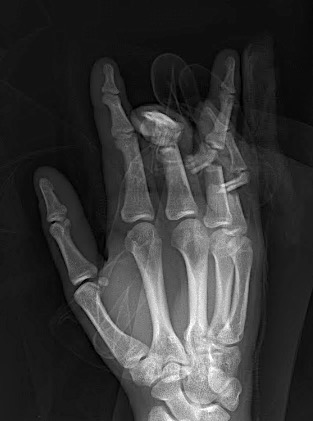

Case 1:

A 64-year-old male suffered a multi-fragmentary fracture of his right thumb metacarpal (Fig 1). An adapted 12-hole strut plate from the variable angle locking hand system was the implant of choice for fixation (Figs 2 - 4).

The strut plate provided good stability in a comminuted extraaricular fracture pattern and enables immediate mobilization. Bone callus formation was not witnessed during the healing process.